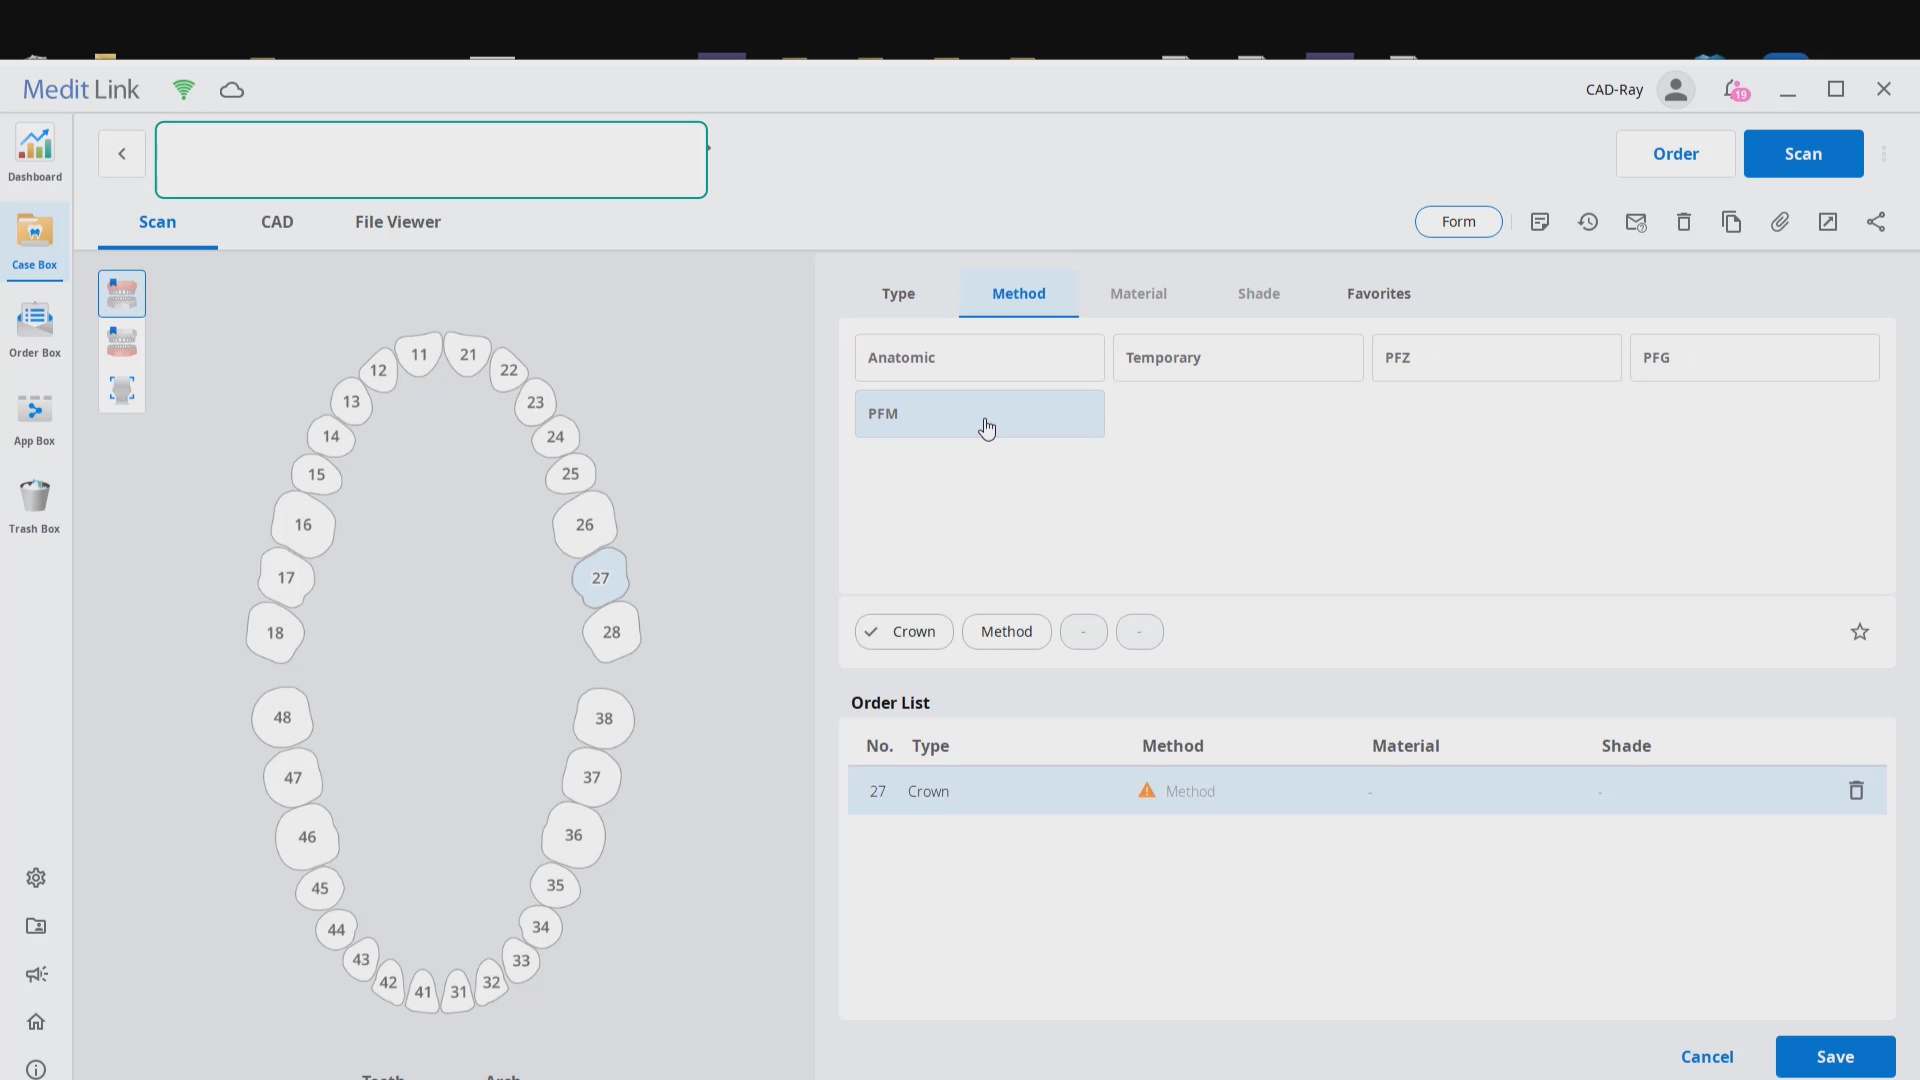

Using the CT as a Remount Jig If You Have Lost The Vertical Dimension For Some Reason or Another

November 20, 2020At CAD-Ray, we have now designed over 20,000 implant cases since 2013. One of the most common requests we get is from doctors doing full arches and their desires to […]